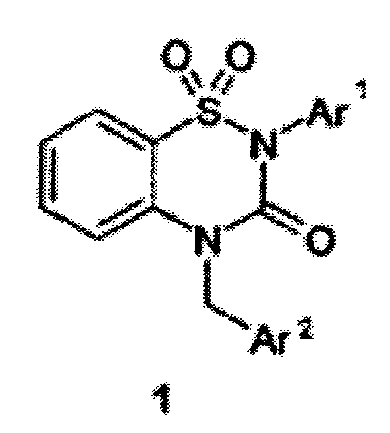

| 16. | 1. | 2574397 (21), (22) Заявка: 2015104887/04, 13.02.2015 (24) Дата начала отсчета срока действия патента: 13.02.2015 (45) Опубликовано: 10.02.2016 (51) МПК C07D285/18, A61K31/54, A61P31/14 (72) Авторы: Иващенко Александр Васильевич, Иващенко Андрей Александрович, Бычко Вадим Васильевич, Хват Александр Викторович, Савчук Николай Филиппович, Роговой Борис (73) Патентообладатель: Иващенко Александр Васильевич, АЛЛА ХЕМ, ЛЛС Адрес для переписки: 141401, Московская обл., г. Химки, ул. Рабочая, 2а, корп. 1, ЦВТ "ХимРар", Шмаковой Е.А. (54) Бензо[1.2.4] тиадиазиновые ингибиторы репликации вируса гепатита В и фармацевтическая композиция для лечения гепатита В |

Изобретение относится к новым ингибиторам репликации вируса гепатита В, представляющим собой 1,1-диоксо-1,4-дигидро-2Н-бензо[1,2,4]тиадиазин-3-оны общей формулы 1, их фармацевтически приемлемые соли и/или гидраты. В общей формуле 1

где

где  и

и  представляют собой фенил, необязательно замещенный одним, двумя или тремя одинаковыми или различными заместителями, выбранными из

представляют собой фенил, необязательно замещенный одним, двумя или тремя одинаковыми или различными заместителями, выбранными из  , метоксила, галогена, карбоксила и карбонитрила. Изобретение также относится к фармацевтической композиции в форме таблеток, капсул или инъекций, помещенных в фармацевтически приемлемую упаковку, для лечения гепатита В и к способу профилактики или лечения гепатита В.

, метоксила, галогена, карбоксила и карбонитрила. Изобретение также относится к фармацевтической композиции в форме таблеток, капсул или инъекций, помещенных в фармацевтически приемлемую упаковку, для лечения гепатита В и к способу профилактики или лечения гепатита В.